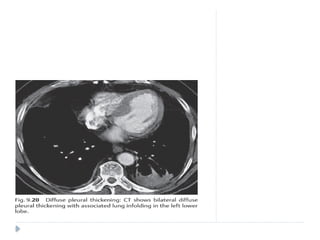

 Pleural thickening is common and is usually a sequel of

pleural inflammation.

 It may also be a delayed complication of hemothorax,

pleural empyema, and recurrent pneumothorax.

 Localized pleural thickening is frequently found at the

bases and results in blunting of the costophrenic angles

with tenting of the diaphragmatic pleura .